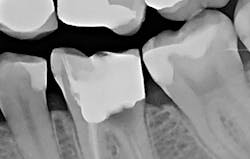

The patient presented with tooth No.19 ML with a history of endodontic treatment fractured to the level of the alveolus (figures 6-8). The patient had an inadequate clinical crown to restore. The options were either to extract the tooth and place an implant, or complete a crown lengthening and then restore. The clinical objective of crown lengthening was to establish biologic width and expose enough tooth structure coronal to the bone for a proper restoration. The patient opted for crown lengthening, and the procedure was completed in about 50 minutes.

The patient was anesthetized with 1.7 ml of 4% articaine with epinephrine 1:100,000. The entire procedure was performed using the "Hard and Soft Tissue" setting. The gingiva was flapped to expose bone using the 0.25 mm spot size with 1% mist and cutting speed between 20% and 50% (figures 9-10). Only 0.5 mm of tooth structure was coronal to the alveolar bone. The osseous tissue was removed to establish biologic width and expose tooth structure coronal to bone for a proper restoration (figure 11). Proper positive bony architecture was maintained. The 0.75 mm spot size was used with 100% mist and cutting speed between 30% and 60%. A temporary restoration was placed, followed by one suture (figure 12). The total procedure time was 50 minutes. The patient was reevaluated after seven days (figure 13), and the final crown was placed (figure 14).

With traditional instruments, this procedure is typically completed with a scalpel and high-speed handpiece with burs. A larger flap is required to improve visibility and instrumentation. However, with Solea's precision and small spot-size options, a much smaller flap was needed. There was less bleeding, resulting in a cleaner surgical site and faster postoperative healing. As the radiograph and photos show, excellent conditions for the final restoration were established. The final crown demonstrated sound margins and evidence of proper biologic width. As the five-day follow-up photo shows, the healing time was fast, and tissues appear healthy.